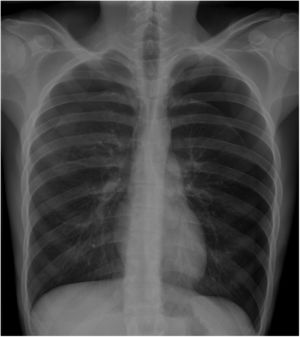

We report the case of a 19-year-old man with no significant medical history who attended the emergency room with a history of several hours of dyspnea and chest pain. Physical examination revealed bilateral reduced breath sounds, and chest X-ray showed bilateral pneumothorax (Fig. 1). The patient was treated with chest drains and scheduled for urgent surgical intervention. Preoperative evaluation revealed partial factor VII deficiency, which was corrected prior to surgery. Consecutive bilateral video-assisted thoracoscopy was performed which showed apical bullae consistent with emphysema. Atypical segmentectomy and mechanical pleurodesis were performed. The patient was discharged on postoperative day 5, after requiring replacement of a chest tube for right pneumothorax due to untimely withdrawal of the surgical drain.